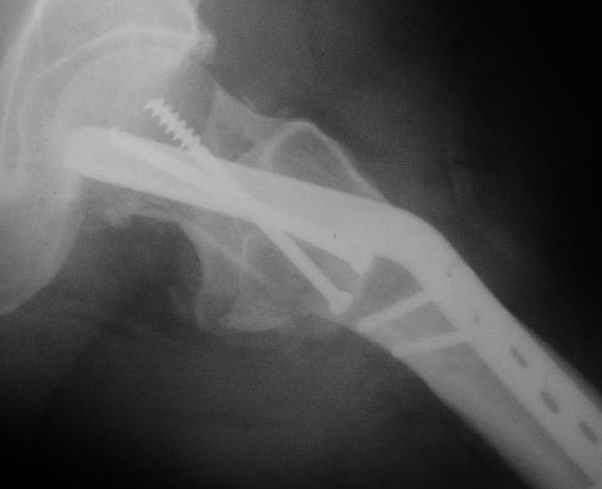

Мужчину 56 лет оперировали у нас в августе 2003 г. - вальгизируюшая остеотомия из-за позднего (через 2 мес. после травмы) поступления с переломом шейки бедра (картинки 1,2). Курильщик, соматической патологии не было. Сейчас поступил с жалобами на проблемы в области тазобедренного сустава, на снимках 3,4 видно вырезывание клинка.Чтоб можно посоветовать в этой ситуации? Заранее спасибо.

A male 56 years old was operated in Aug 2003 - valgus osteotomy performed because of delayed admission with neck fracture (2 months) images 1,2. Smoker, no other major medical problem. Now he re-admitted with the images 3,4.What would you do in the situation?THX in advance.

The osteotomy seems to be showing bony union. (New bone at the medial aspect). There is a big step in the union. The distal fragment is way out laterally.There is overiding of the neck over the head. The screws are out superiorly and the blade also coming out. There is no union of the neck fracture. The head does not seem to be normal- distorted in shape and probably starting of AVN too.

It will be a futile attempt now to get the neck fracture unite. The head has to come out and has to be replaced. Then comes the problem of the malaligned upper shaft. If it has united ( as what I think now) the union has to be undone and fragments aligned before introducing the stem.

If replacement is considered, the osteotomy has to be realigned as mentioned earlier.